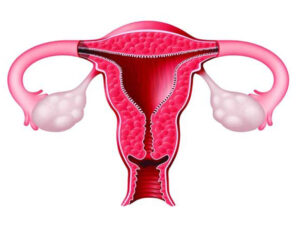

لاپاراسکوپی کیست تخمدان یکی از روشهای جراحی برای برداشتن کیستهای درون تخمدانها به حساب میآید. کیستهای تخمدان تودههایی هستند که در اثر دلایل مختلف ممکن

هیستروسکوپی میومکتومی یکی از روشهای کمتهاجمی و موثر برای درمان فیبرومهای رحمی (میومها) است که با استفاده از یک دستگاه نازک و دوربیندار به نام

آیا به دنبال روشی موثر برای درمان اندومتریوز هستید و با درد و ناراحتی دست و پنجه نرم میکنید؟ این بیماری پنهان میتواند زندگی روزمره،